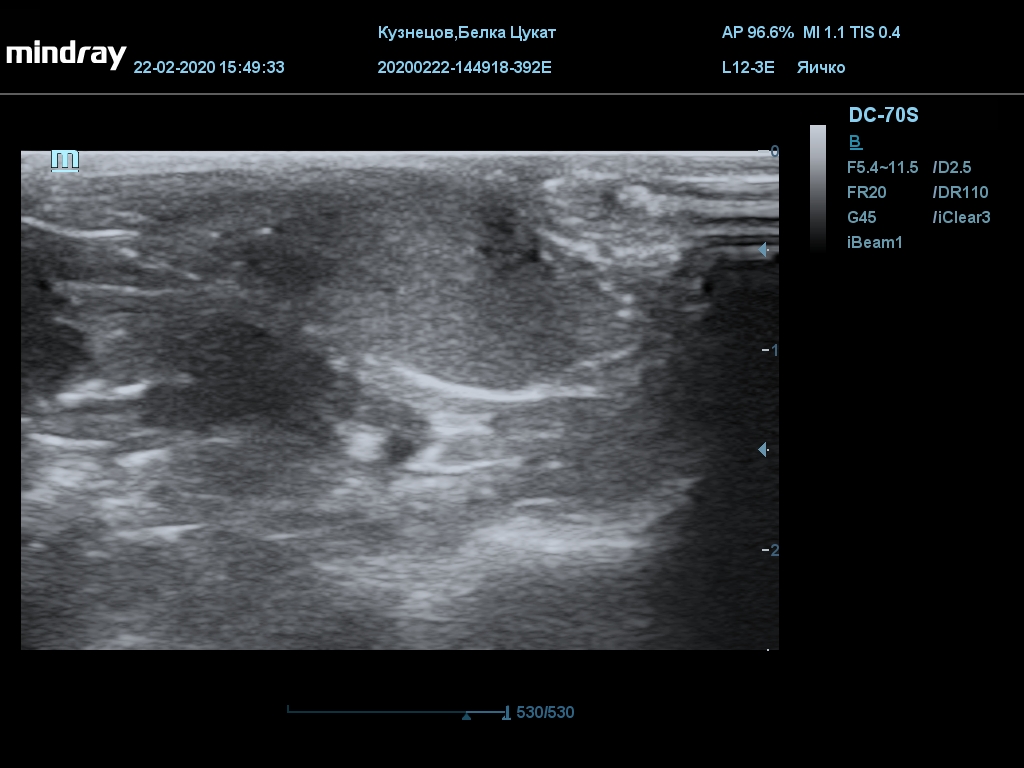

УЗИ

(почки, мочевой пузырь и, предположительно, простата)

Обращаю внимание, что делала УЗИ и писала заключение узист, которая специализируется на кошках и собаках, поэтому она сделала узи и описала, как смогла, но тонкостей грызунячьей анатомии она не знает.

Приложил только фото, есть ещё пара видео, но не знаю, как тут выложить, и надо ли.

Мочевой пузырь объём 12,1 х 7,6 х 11 мм. Стенка не утолщена, 0,5 мм, содержимое не однородное, до половины объёма гипоэхогенная мелкодисперсная взвесь. Макс. размер включений 0,8 мм. Теней нет.

Каудальнее мочевого пузыря визуализируется округлая структура размером 11,1 х 8,3 мм с ровными контурами гипоэхогенная однородная, с признаками васкуляризации.

Почка левая ровная, размер 12 х 7,6 х 8,2 мм. Контур ровный чёткий. КМД отсутствует, лоханка расширена незначительно, объёмных включений не выявлено.

Почка правая ровная, контур чёткий, размер 13,5 х 8,7 х 9,3 мм. Капсула визуализируется. КМД отсутствует, лоханка не расширена. Объёмные образования не выявлены.

Заключение: УЗпризнаки уролитиаза, объёмная структура каудальнее мочевого пузыря. Признаки расширения левой лоханки.

УЗИ

(почки, мочевой пузырь и, предположительно, простата)

Обращаю внимание, что делала УЗИ и писала заключение узист, которая специализируется на кошках и собаках, поэтому она сделала узи и описала, как смогла, но тонкостей грызунячьей анатомии она не знает.

Приложил только фото, есть ещё пара видео, но не знаю, как тут выложить, и надо ли.

Мочевой пузырь объём 12,1 х 7,6 х 11 мм. Стенка не утолщена, 0,5 мм, содержимое не однородное, до половины объёма гипоэхогенная мелкодисперсная взвесь. Макс. размер включений 0,8 мм. Теней нет.

Каудальнее мочевого пузыря визуализируется округлая структура размером 11,1 х 8,3 мм с ровными контурами гипоэхогенная однородная, с признаками васкуляризации.

Почка левая ровная, размер 12 х 7,6 х 8,2 мм. Контур ровный чёткий. КМД отсутствует, лоханка расширена незначительно, объёмных включений не выявлено.

Почка правая ровная, контур чёткий, размер 13,5 х 8,7 х 9,3 мм. Капсула визуализируется. КМД отсутствует, лоханка не расширена. Объёмные образования не выявлены.

Заключение: УЗпризнаки уролитиаза, объёмная структура каудальнее мочевого пузыря. Признаки расширения левой лоханки.